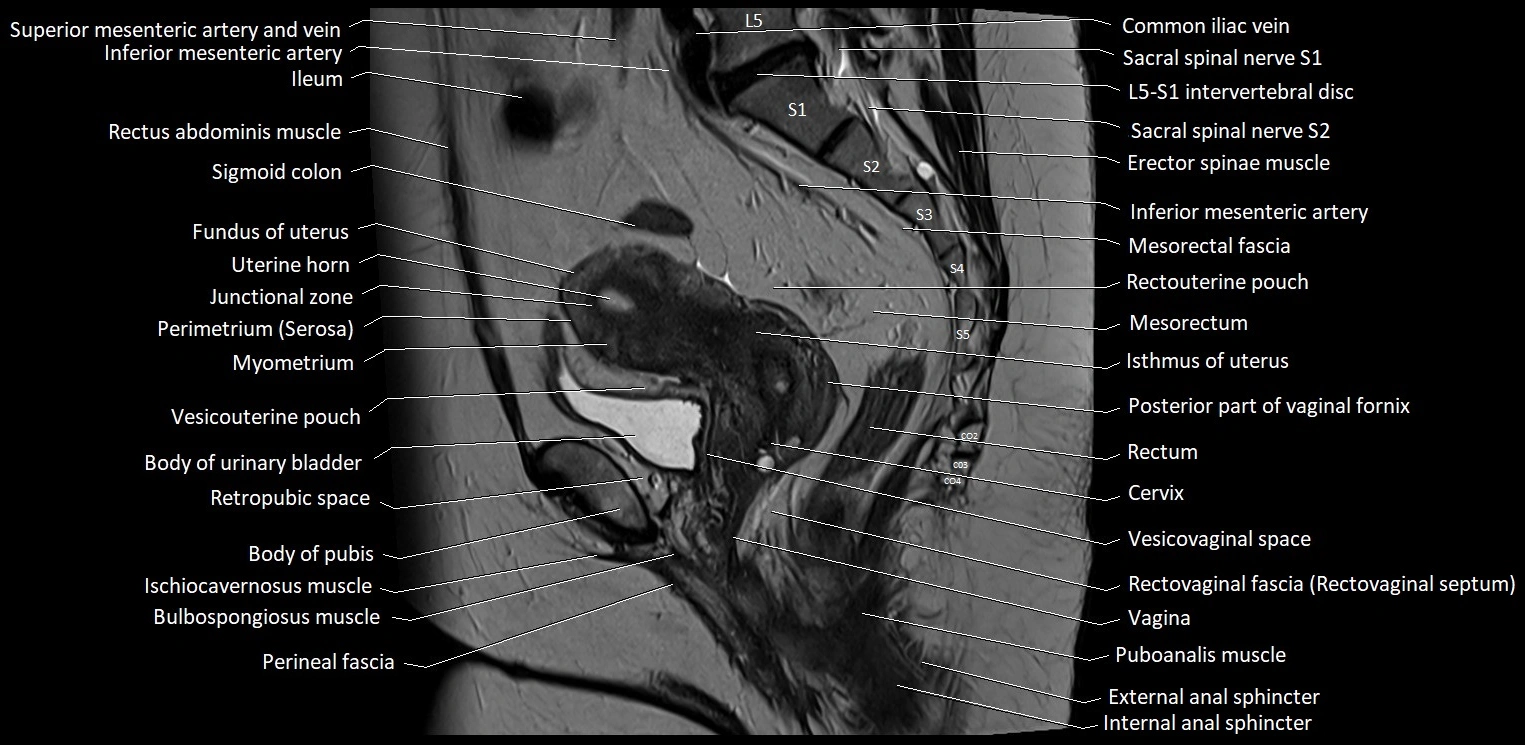

- Body of urinary bladder

- Cervix of uterus

- Common iliac vein

- Erector spinae muscles

- Fundus of uterus

- Ileum

- Inferior mesenteric artery (IMA)

- Isthmus of uterus

- Junctional zone of uterus

- Mesorectal fascia

- Mesorectum

- Myometrium of uterus

- Perimetrium of uterus

- Posterior fornix of cervix

- Puboanalis muscle

- Rectouterine pouch (pouch of Douglas)

- Rectovaginal septum (rectovaginal fascia)

- Rectum

- Retropubic space

- Vagina

- Vesicouterine pouch

- Vesicovaginal space